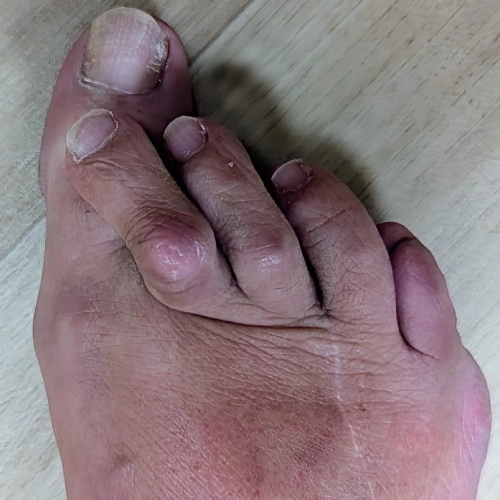

Bunion treatment to correct toe alignment and relieve foot painBunion treatment to correct toe alignment and relieve foot pain

Bunion treatment to correct toe alignment and relieve foot painTreatment for bunions improving comfort and walking ability

Treatment for bunions improving comfort and walking abilityTreatment for bunions improving comfort and walking ability